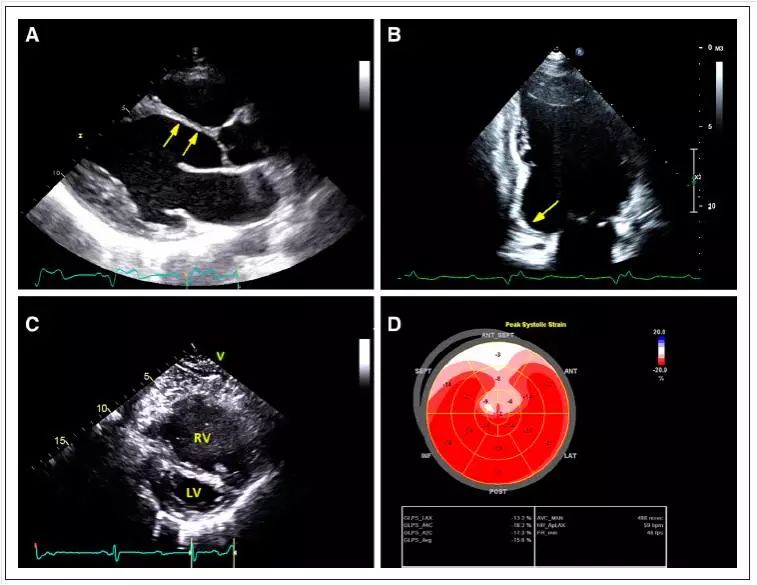

心肌结节病 ECHO:A 前间隔变薄; B 下壁基部瘤样扩张;C 肺动脉高压,右室大 ; D 左室整体收缩期纵向峰值应变(室间隔及心尖部重度减低,其他部位轻度减低)

(CircRes.2017;121:819-837)